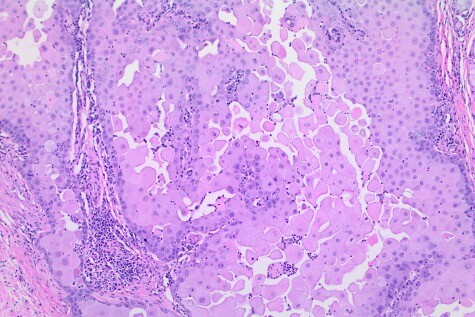

ISVD cases are a great way to review histopathology, and correlate histopath findings with clinical cases (complete with case images and history). Thanks so much to the ISVD for this great resource!